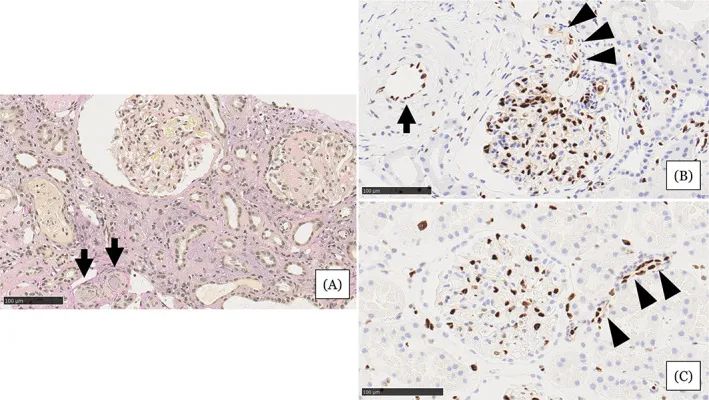

圖注:在住院第31天進行的腎活檢結果。A,顯示小動脈被粘液性內膜增厚(箭頭)堵塞,腎小球萎縮,毛細血管壁起皺,嚴重的間質單核細胞浸潤伴腎小管損傷。B,EC細胞核的缺乏在小動脈(箭頭)中很突出。在相鄰的小動脈(箭頭)中注意到不同大小的不規則細胞核。C,EC的等距核在血壓正常的腎臟供體的腎臟小動脈中形成有序的線。比例尺 =100μm

研究人員從患者身上收集干細胞后,并將其直接注入雙側腎動脈。細胞移植后除了出現一過性發熱和血小板增多外,未出現任何重大不良事件。細胞移植后23周,他的血清肌酐水平顯著改善(提高至2.96mg/dL),此外僅用60mg硝苯地平和20mg奧美沙坦便可以很好地控制之前難以控制的頑固性高血壓。

這項醫學實驗初步證實了干細胞療法對于治療急性腎損傷是安全有效的。